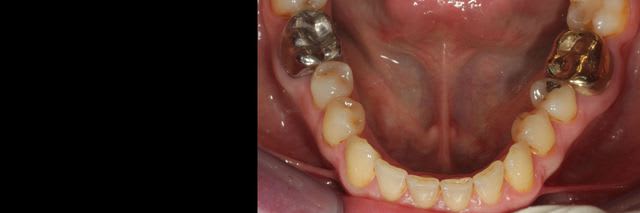

Cette patiente vient me voir pour trouver une solution pour sa 15, que proposez vous?

J'ai décidé de réaliser un lambeau déplacé latéralement associé à un conjonctif enfoui le jour de l'extraction afin d'avoir des tissus mous de meilleure qualité pour la greffe, ci joint les photos à 6 semaines.